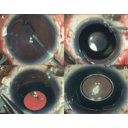

Recursos para afaquia mauricio rivera gonzalez 3TM1

afaquia0.jpg

lente intraocular0.jpg